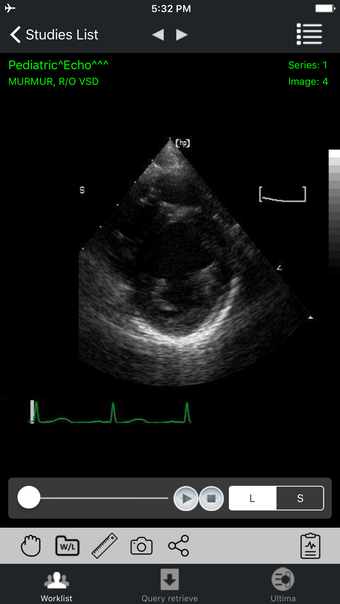

iPaxera is a user-friendly PACS viewing application designed for iOS devices, offering seamless navigation of DICOM images. It allows adding studies from PCs, DICOM CDs, or flash memory directly to your iPhone or iPad via iTunes synchronization. iPaxera boasts a direct interface with PaxeraView, enhancing diagnostic viewing capabilities. The app features an embedded reporting tool for report writing, email sending, or report saving alongside the study. Users can leverage a generic speech recognition tool for dictation. iPaxera supports DICOM Cine with interactive playback controls, particularly useful for Cardiac Cath and Echo studies. With an interactive worklist, specific search criteria, and essential study information, iPaxera ensures easy study management and visualization.

Key features include study synchronization via iTunes, an intuitive reporting tool, interactive image navigation, zooming, panning, rotation, and distance measurement. Users can adjust window width and level with simple gestures and reset images with a double tap.